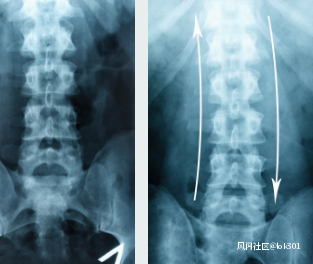

1.骨性結構變異壓迫 ①發育性腰椎管狹窄,如椎板或黃韌帶肥厚引起的神經壓迫綜合徵及側隱窩狹窄引起的神經根壓迫;②強直性脊椎炎,其可合併蛛網膜炎,繼而形成憩室樣囊腫並不斷擴大,導致椎管擴大,椎體後部、椎弓和椎板骨質壓迫性缺損,蛛網膜囊腫形成,因而導致脊髓圓錐或(和)馬尾神經受壓;③腰椎退變性脱位或腰椎骨折,椎板下緣及附着在鬆弛椎板上的黃韌帶増厚,骨嵴増生,圍繞硬脊膜及側隱窩內的纖維組織可壓迫馬尾神經及神經根。骨折塊或破碎的椎間盤等可佔據椎管內空間直接壓迫馬尾神經。骨折塊也可穿入硬膜內造成馬尾神經直接損傷,出血、瘢痕化,椎體壓縮性骨折致構成椎管的軟組織向椎管內皺褶,椎管極度狹窄。可產生嚴重的或不可逆轉的馬尾神經損傷症狀。

2.軟組織壓迫腰椎間盤突出症和腰椎管狹窄症引起馬尾神經受損 腰椎間盤突出症合併馬尾神經損傷的發生率為7%左右。曾報道根袖段神經根營養的75 %來自腦脊液,25%來自血供,因此腦脊液受阻時營養大部分喪失。馬尾神經水腫消退後周圍粘連形成,即便行椎板切除,突出物摘除減壓,一段時間內腦脊液循環仍不能建立,使得馬尾神經繼發性損傷繼續加重。